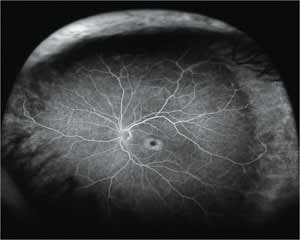

These medications have an affinity for the retinal pigment epithelium (RPE), causing RPE depigmentation and additionally damaging the rod and cone receptors within the macula. This results in the classic funduscopic presentation of bull's-eye maculopathy (Figure 1). Even with prompt discontinuation of these medications, vision often deteriorates further for up to several years.1

Figure 1. Ultra-widefield fluorescein angiography exhibits hydroxychloroquine toxicity with “bull's eye” maculopathy.

COURTESY: JOHN W. KITCHENS, MD